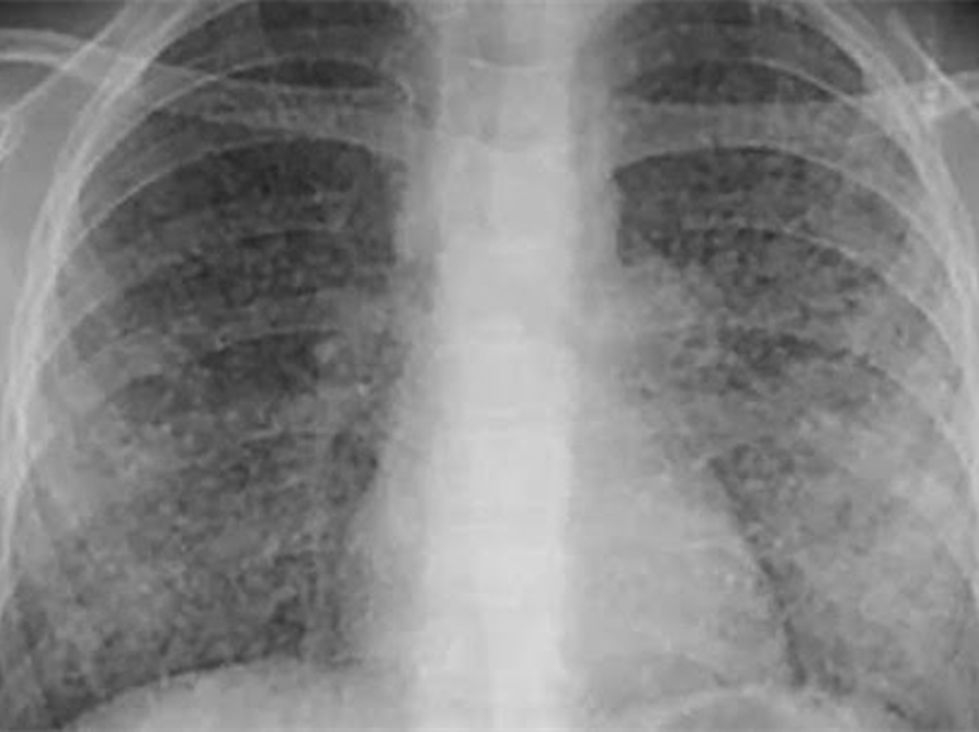

Bệnh lao kê là một thể lao cấp tính nặng thường ít gặp, do vi khuẩn lao Mycobacterium tuberculosislan tràn vào đường máu với số lượng lớn. Lao kê có thể là bệnh thứ phát hoặc là tiên phát, với dấu hiệu đặc trưng là khi quan sát khắp phổi xuất hiện những hạt nhỏ như kê với đường kính khoảng 1 – 3 mm.

- Chụp CT, MRI phổi;